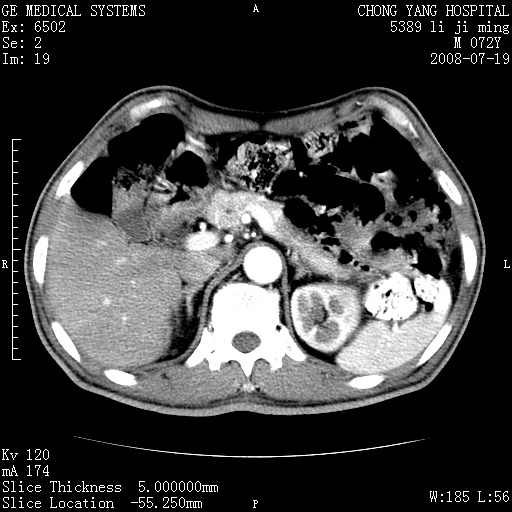

以下是引用zjzjr在2008-7-19 20:57:00的发言:[br]胰头增大,边缘模糊,周围可见渗出影,右侧肾前筋膜增厚.支持胰腺炎.

以下是引用yangyudong333在2008-7-20 6:56:00的发言:[br]胰腺增大尤以胰头明显,边缘模糊,周围可见渗出影,右侧肾前筋膜增厚,肠管於涨.支持胰腺炎

以下是引用不学无术在2008-7-19 23:15:00的发言:[br]胰腺增大尤以胰头明显,边缘模糊,周围可见渗出影,右侧肾前筋膜增厚,肠管於涨.支持胰腺炎